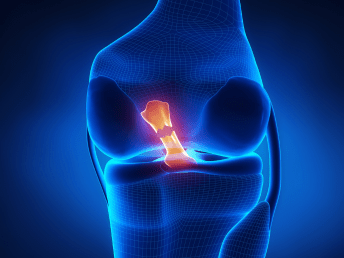

Best ACL & Ligament Surgeon in Ranchi

Looking for the best specialist to treat ACL or ligament injuries in Ranchi? Dr. Ankur Saurav, a highly experienced and trusted orthopedic surgeon, is known for delivering exceptional outcomes in ACL reconstruction and ligament surgeries. Using modern surgical methods, tailored treatment strategies, and a compassionate, patient-centered approach, Dr. Ankur Saurav ensures faster recovery and long-term joint stability. Whether you're an athlete recovering from a sports injury or someone dealing with knee instability, Dr. Ankur Saurav—the best ACL & ligament surgeon in Ranchi—offers expert care to get you back on your feet with confidence.